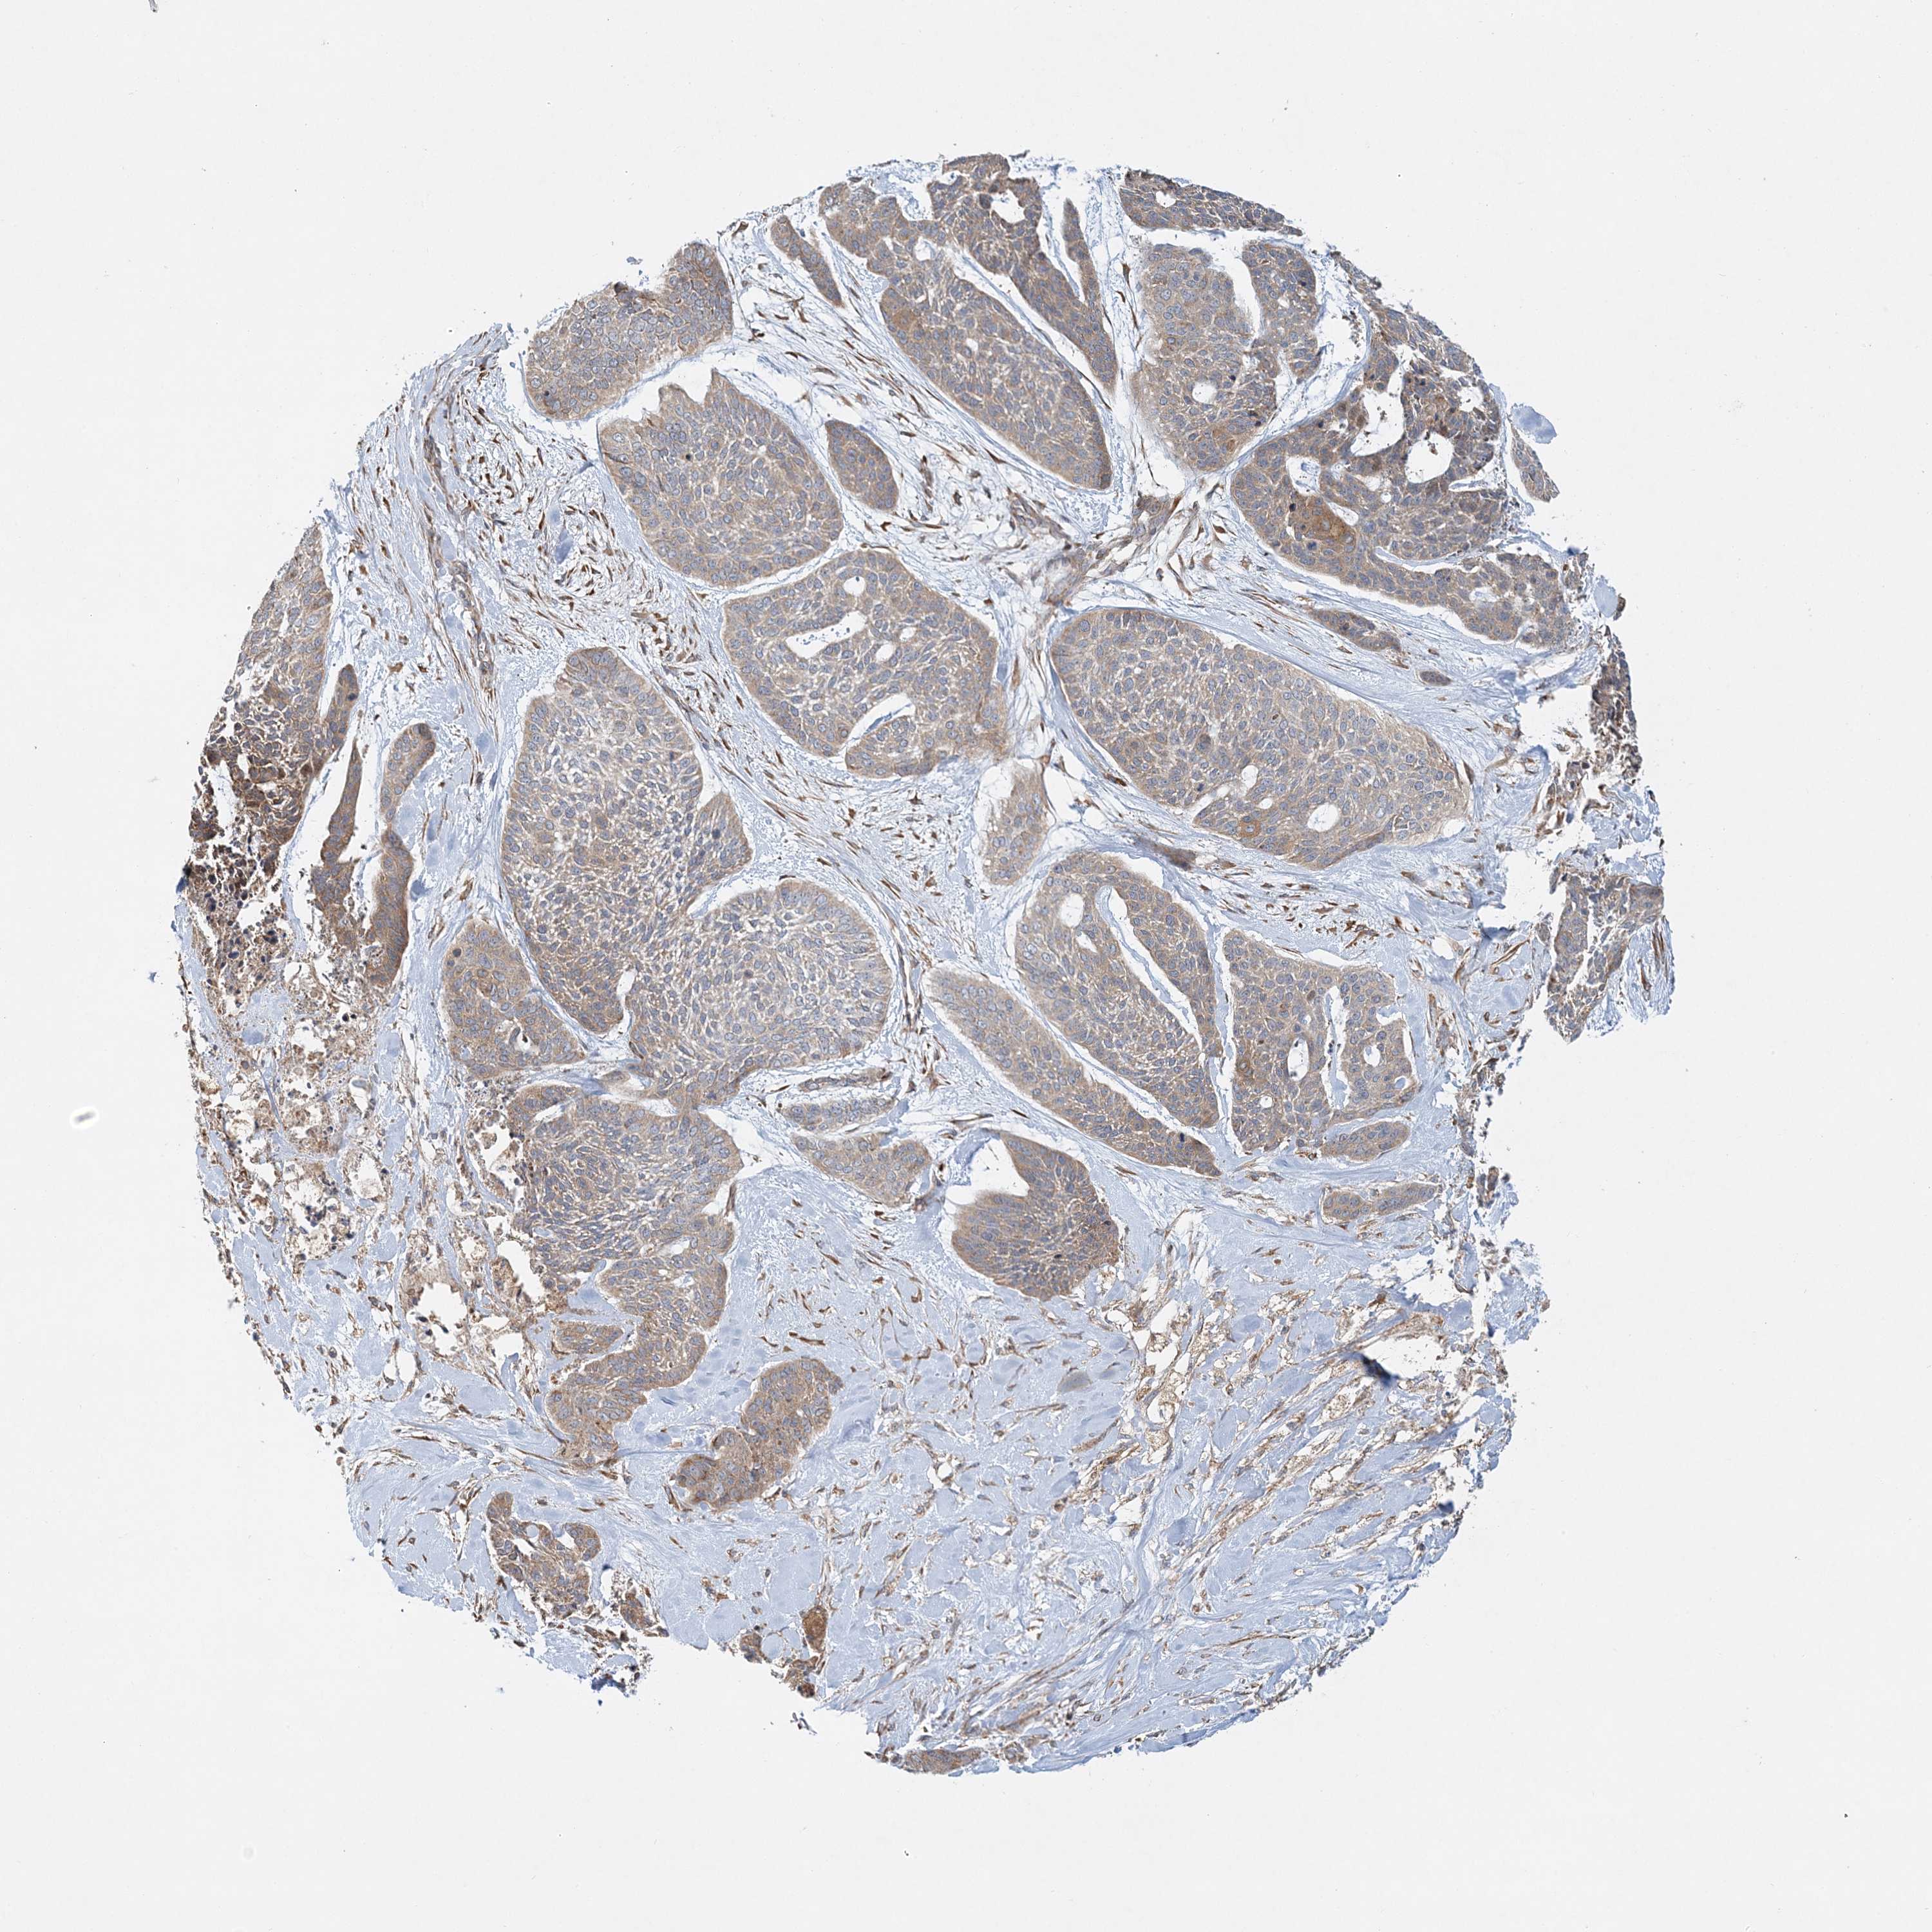

SKIN CANCER - Protein expressioni

A mouse-over function shows sample information and annotation data. Click on an image to view it in a full screen mode. Samples can be filtered based on level of antibody staining by selecting one or several of the following categories: high, medium, low and not detected. The assay and annotation is described here.

Antibody staining in the annotated cell types in the current human tissue is reported as not detected, low, medium, or high, based on conventional immunohistochemistry profiling in selected tissues. This score is based on the combination of the staining intensity and fraction of stained cells.

Each image is clickable and will lead to virtual microscopy that enables deeper exploration of all samples and also displays staining intensity scores, fraction scores and subcellular localization as well as patient and tissue information for each sample.

Antibody HPA035935

Basal cell carcinoma